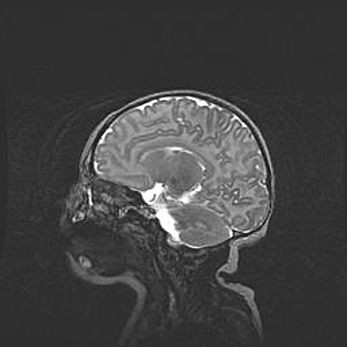

Аномалия Денди-Уокера. Признаки гипоплазии мозолистого тела.

Возраст: 5 месяцев 3 дня

Вес: 5550 г

Пол: мужской

Окружность головы: 39 см

Срок гестации: 40 недель

Аномалия Денди-Уокера – это порок развития головного мозга, для которого характерна триада симптомов: гипотрофия или аплазия червя мозжечка и/или полушарий мозжечка, расширение четвёртого желудочка с формированием ликворной кисты задней черепной ямки, гипертензионная гидроцефалия различной степени.

Гипоплазия мозолистого тела относится к дефектам внутриутробного этапа развития мозговой ткани, возникающим в процессе закладки структур головного мозга, что происходит на начальных этапах развития эмбриона.